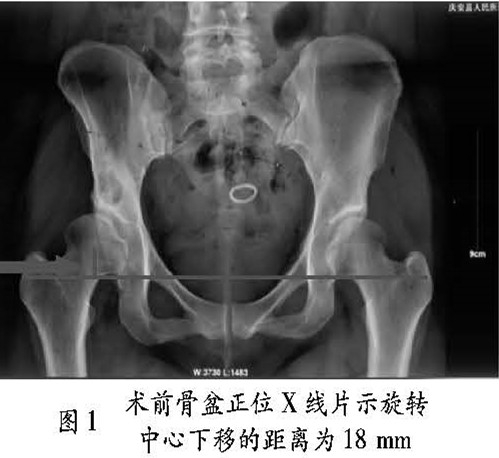

典型病例: a) 25 岁女性患者,右侧髋白发育不 良, 右侧髋关节略有疼痛症状 2 年,轻度跛行, Harris 评分为 75 分,行右侧髋曰旋转截骨术。术后旋转中心由术前的 18 mm 下降至 15 mm,手术前后影像学资料见图 1 ~2。